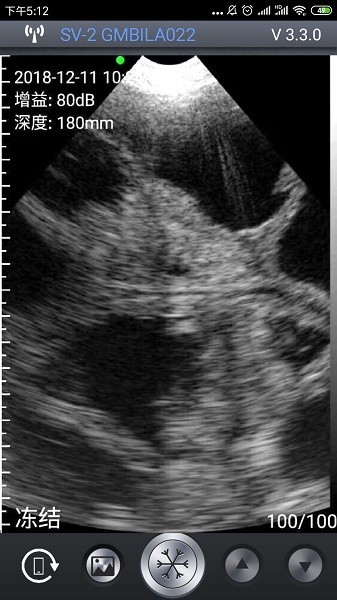

2、 成像精准:配套硬件协同工作,呈现高清晰度图像,辅助准确判断母猪怀胎情况。

2、实时图像显示:即时呈现超声扫描画面,便于快速查看与初步判断检测结果。

3、图像处理工具:集成画面放大、对比度调节、区域截图等多种影像增强功能。